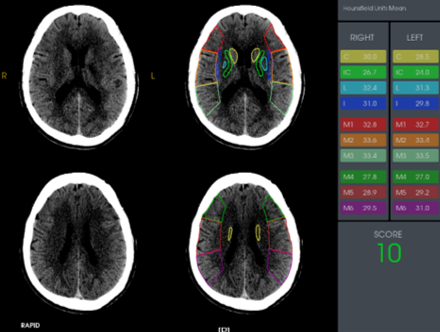

近期,我院高級(jí)卒中中心引進(jìn)了腦卒中頭顱“一站式”ct檢查又稱多模式頭顱ct成像,包括ct平掃(ncct),ct血管成像(cta)和ct灌注成像(ctp)。目前省內(nèi)僅有我院及中南大學(xué)湘雅醫(yī)院、湘潭市中心醫(yī)院三家醫(yī)院應(yīng)用了該項(xiàng)技術(shù)。該項(xiàng)技術(shù)的目的是擴(kuò)大取栓治療時(shí)間窗,使更多的患者從取栓治療中獲益。通俗的說(shuō),“時(shí)間就是大腦”的搶救理念倡導(dǎo)的是,一旦發(fā)生卒中征兆,立即送至有靜脈溶栓、機(jī)械取栓資質(zhì)的醫(yī)院救治。對(duì)于明確發(fā)病4.5h以內(nèi)的急性缺血性腦卒中患者,來(lái)了醫(yī)院之后先做一個(gè)ct平掃檢查,排除腦出血的情況,在無(wú)禁忌癥的前提下,建議實(shí)施靜脈溶栓治療,早發(fā)現(xiàn)早治療早獲益。但是對(duì)于發(fā)病6-24h的患者或發(fā)病時(shí)間不明確的患者,ct平掃上是很難看到梗死表現(xiàn),梗死的表現(xiàn)一般到24小時(shí)之后才會(huì)出現(xiàn)。那怎么來(lái)顯示這部分組織?那就是進(jìn)行“ct灌注成像”,可以看到具體的梗死區(qū)域、可挽救的缺血半暗帶、同時(shí)利用ctp數(shù)據(jù)進(jìn)行頭部cta重建和側(cè)枝循環(huán)評(píng)估,為下一步的治療方案提供量化標(biāo)準(zhǔn)。但是做ct、cta再做ctp無(wú)疑時(shí)間線就拉長(zhǎng)了,與“時(shí)間就是大腦”的理念相違背。那有沒(méi)有一項(xiàng)技術(shù)將這三項(xiàng)檢查緊密聯(lián)系起來(lái),有效縮短檢查時(shí)間?這便是頭顱“一站式”ct檢查,既為腦卒中患者的救治贏得了寶貴的時(shí)間,又如同徠卡相機(jī)一樣精準(zhǔn)、高清的成像,幫助醫(yī)生快速擬定治療方案。

多模式頭顱ct成像和側(cè)枝循環(huán)評(píng)估